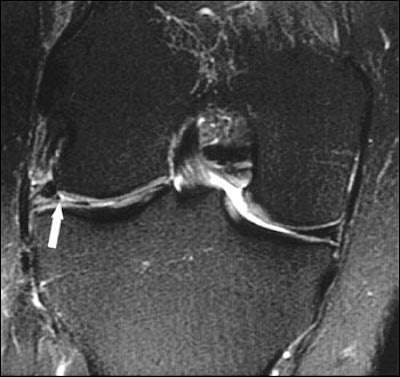

| Twenty-eight-year-old man with knee pain after surgery. Patient had surgically proven meniscal radial tear. Above, proton density-weighted sagittal MR image (TR/TE, 1,800/12) shows findings consistent with meniscal radial tear (arrow). Below, T2-weighted sagittal MR image (3,950/51) shows linear radial tear (arrow). Magee T, Shapiro M, Williams D, "Prevalence of Meniscal Radial Tears of the Knee Revealed by MRI After Surgery," (AJR 2004, Vol. 182, pp. 931-936). |